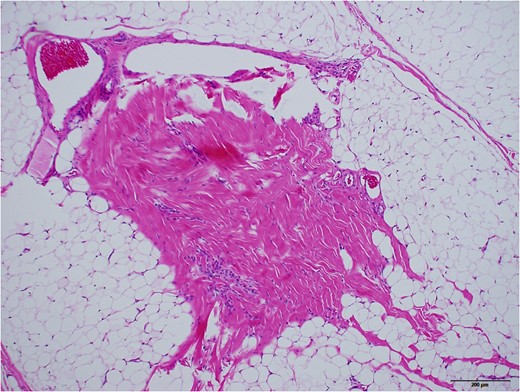

Grossly, protruded part of the mass was covered with sparsely haired skin. Sub-conjunctival part was covered with thin capsule with vasculatures (Fig. 5). Histopathologically, most part of the mass was composed of mature adipose tissue, lobuled by fibrous septum with vasculatures (Fig. 6). Outer surface was covered with squamous epidermis with normal rete ridge. In dermal layer, appendages, including hair follicles, sebaceous glands and sweat glands were seen (Fig. 7). Dense fibrous tissue was seen surrounded by the adipose tissue. This was assumed to be the link of palpebral tarsal plate (Fig. 8). No lacrimal grand tissue was identified.

Dense fibrous part with vasculature, surrounded by adipose tissue, assumed to be the link of tarsal plate. ×10 objective lens. Black bar represents 200 μm.